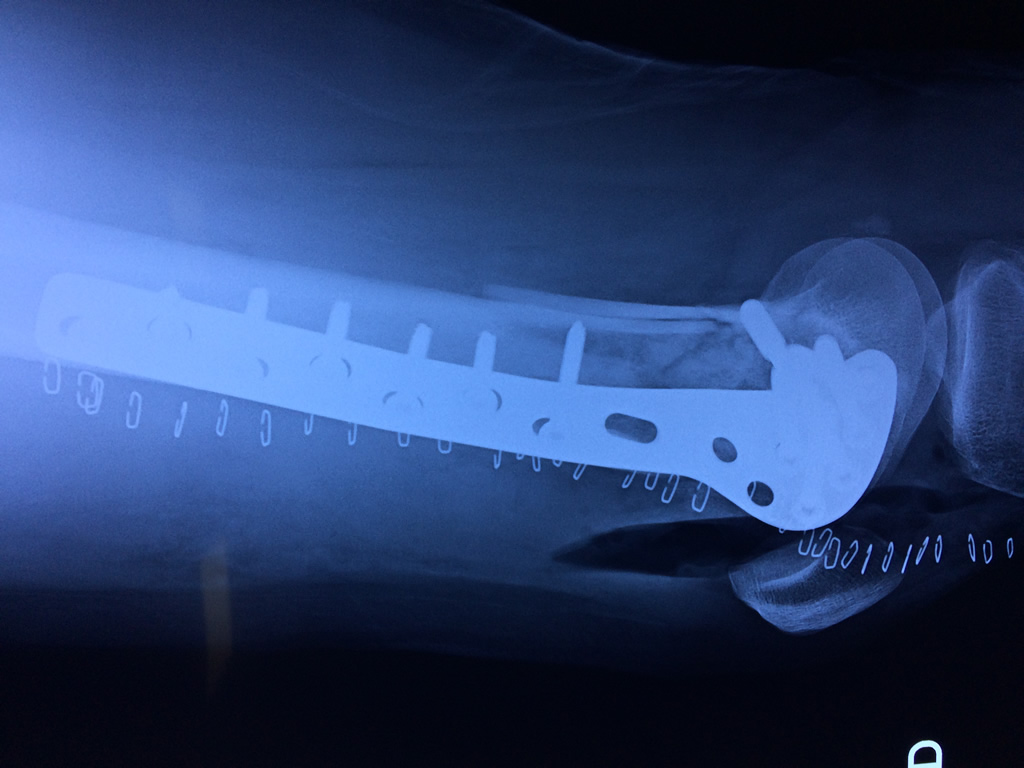

Cirugías de Calcaneo - Fémur

El fémur es el hueso del muslo, el segundo segmento del miembro inferior. Es el hueso más largo, fuerte y voluminoso del cuerpo humano.